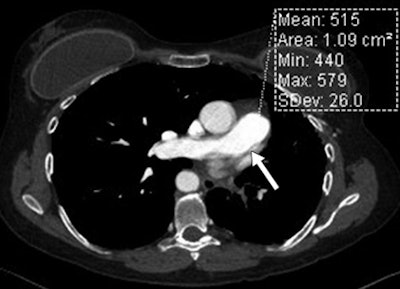

Conventional CTPA acquired without ECG synchronization can suffer from motion artifacts from the heart and vasculature, Bolen and colleagues wrote.

High-pitch CTPA showed higher signal intensity for the pulmonary arteries, and image quality scores demonstrated the technique's superiority for the assessment of cardiovascular structures (p < 0.001), particularly the ability to minimize motion in the central pulmonary arteries (p < 0.001) and deliver greater pulmonary enhancement (p = 0.001). And high pitch did all of this using a significantly lower radiation dose: a mean 2.9 ± 1.4 mSv for high-pitch scanning versus 6.1 ± 2.9 mSv (p < 0.001) for conventional CTPA.